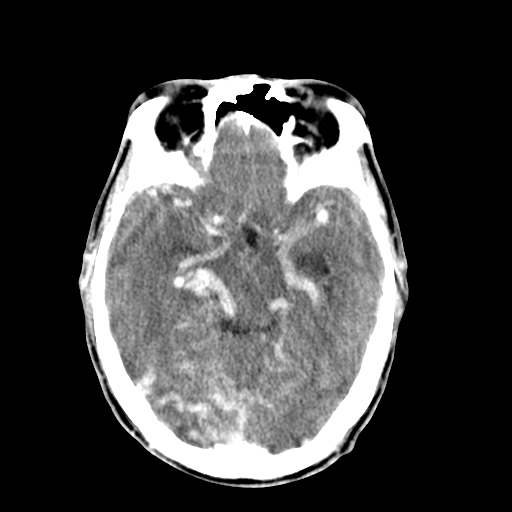

标题: CT17002:M48Y,血管畸形,血管瘤,请鉴赏! [打印本页]

男48y,头痛多年,加重一天!

典型的血管畸形---avm  -----右侧枕顶叶及侧脑室三角区等高混杂密度影夹杂少许低密影显示,无明显水肿,增强可见明显的供血动脉与引流静脉显示